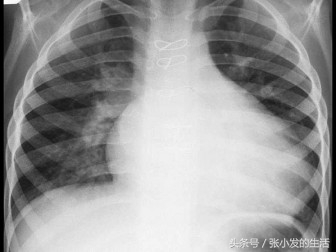

51[单选题]女孩11岁,胸骨左缘第2肋间听到Ⅱ级收缩期杂音,肺动脉瓣区第二心音固定分裂。胸片示如图,右房右室增大。心电图为不完全右束支阻滞,最可能的诊断是 ( )

A.房间隔缺损

B.室间隔缺损

C.肺动脉狭窄

D.法洛四联症

E.动脉导管未闭

正确答案:A